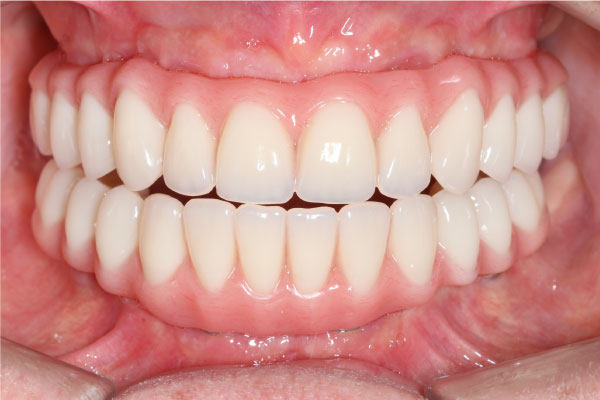

Имплантация зубов: фото «До» и «После»

Фото ДО

Фото ПОСЛЕ

All-on-4